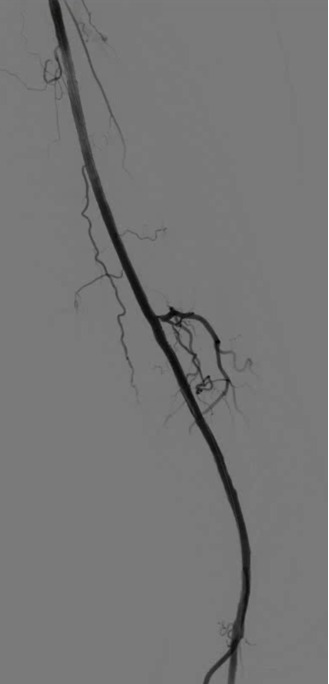

★ 病例2

51岁男性,间歇性跛行反复发作,经历多次PTA、CDT、支架植入等复杂治疗

2019.07 间歇性跛行3个月,PTA+CDT(8天)

2022.05,足趾麻木,支架植入

2023.05,间歇性跛行3个月,PTA+支架植入

治疗心得:50岁以上患者诊断困难;病灶进展迅速,治疗间隔缩短,难度增加;完全戒烟至关重要,但临床依从性差